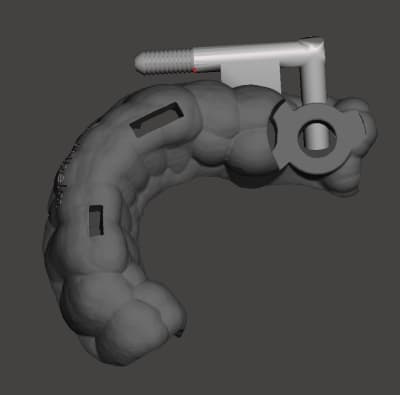

exemple de guide, pour quasi le meme cas : guide resine a apuis dentaire muqueux VS guide appuis dentaire/ osseux.

Avantage posit sans aucun doute sur la ridgidité et la pose de l'implant le plus distal...

c'est dommage que jeff ne poursuive pas la discussion... Hokusai voici le patient qui a bénéficié de ce guide en début de chirurgie (22)

Pourquoi penses tu que le guide est en titane ?

parce qu il est en contact avec l os... alors je me dis qu il doit etre en titane.

mais en meme temps je pense qu il a ete imprime en resine calcinable puis mis en moufle pour être coulé... et que c est chaud de couler du titane.

alors peut etre est il coulé en crco...

je me questionne ;)

En effet le titane coulé c'est très compliqué, j'ai coulé le guide que présente jeff (23) en Cobalt-chrome

non, le chrome cobalt est très résistant, je n'ai jamais eu de casse avec mes guides ajourés. Ils offrent une bonne visibilité contrairement au guide à étage en plastique comme tu peux l'observer avec celui de jeff.